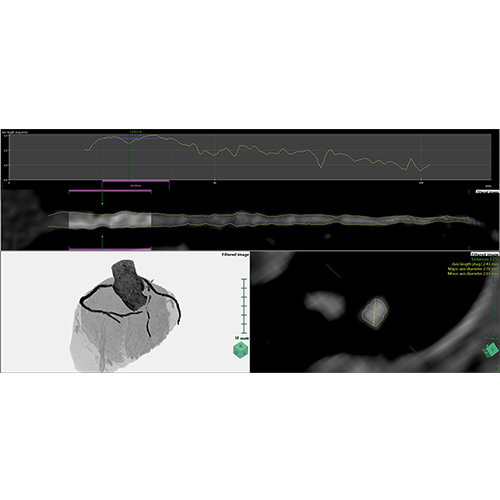

View X-Ray CT & MRI Scans Fast and Easily

Designed for surgeons, Pro Surgical 3D makes it easy to view patient scans quickly. Pro Surgical 3D facilitates the optimal 3D treatment and assessment workflows based on X-ray CT and MRI scans – and best of all, it’s FREE!

High-quality and fast 3D reconstruction and 3D rendering

Performs 3D reconstruction and volume rendering.

Multi-planar slicing.

Oblique slicing.